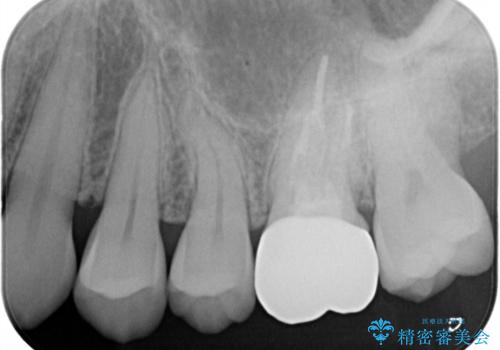

海外転勤が決まり、急いでセラミック治療をしてほしいとご来院された患者様です。

根管治療に症状がなく、上の歯に関しては土台もそのまま使用可能であったため、下の歯の土台、上下の歯のセラミック治療を行いました。

今回は幸い、症状がなく、根管治療の再治療が必要でないため、円滑に治療を進めることができました。